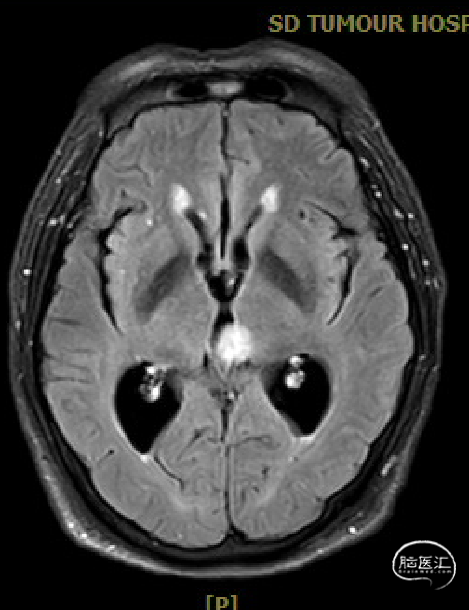

患者5年前无明显诱因出现阵发性头晕,无明显头痛、恶心呕吐等不适,开始未予重视,2022-7-19出现头晕加重,伴视力下降,遂于2022-7-24在当地医院行颅脑MRI提示:松果体区肿瘤伴梗阻性脑积水。

松果体区占位,胶质瘤?生殖细胞肿瘤?

术前MRI与术后复查MRI对比